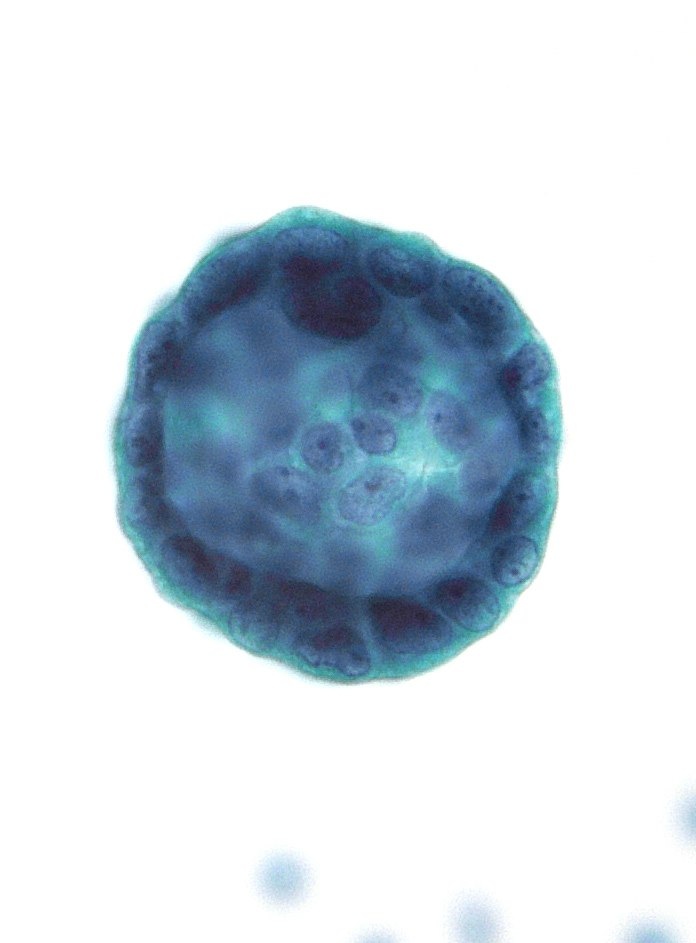

«Пушечные ядра» — классический (но, безусловно, НЕ специфический) цитологический признак метастатической протоковой карциномы молочной железы в серозных выпотах.

Препарат CytoSpin. Объектив 100x.